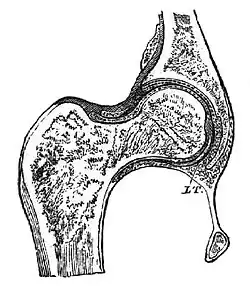

Enartrose

Enartrose ou esferoide é uma articulação em que a superfície em forma de esfera de um osso se encaixa em uma depressão de outro osso. Permite movimento em três eixos: craneocaudal, anteroposterior e laterolateral, permitindo também a circunvolução. No corpo humano existem enartroses no ombro (úmero-escapular), quadril (fêmur-acetabular), no pé (calcâneo-tálus-navicular) e no ouvido médio (entre a bigorna e o estribo).[1]